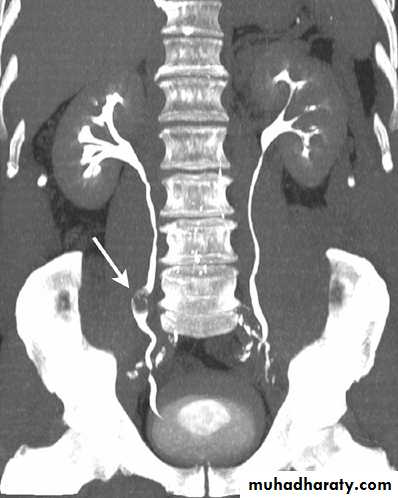

CT scanContrast enhanced CT scan through the kidneys in nephrogram phase 90-100 seconds following contrast administration and would show renal lesions well.

Contrast enhanced CT scan through the kidneys in pyelogram phase (showing excretion of contrast into the collecting system). This is approximately 10-15 minutes following contrast administration and would show urothelial lesions well, such as transitional cell carcinoma, stones, blood clots.